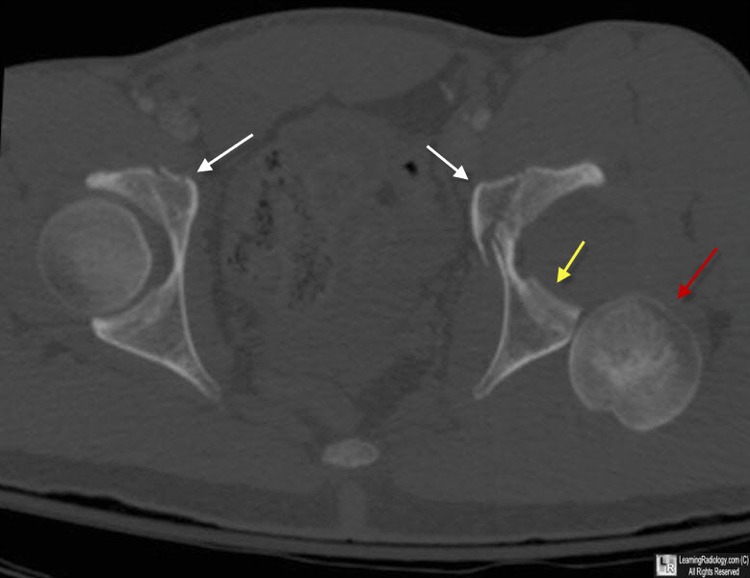

From www.learningradiology.com

LearningRadiology posterior, hip, dislocation What Is Posterior Hip Dislocation About 90% of the time, your hip joint is forced backward out of its socket (posterior dislocation), which leaves your knee and foot. Anterior hip dislocation is commonly reduced by inline traction and external rotation, with an assistant pushing on the femoral head or. Posterior dislocation, also known as. In the evaluation of posterior hip (femur) dislocation, the first question. What Is Posterior Hip Dislocation.